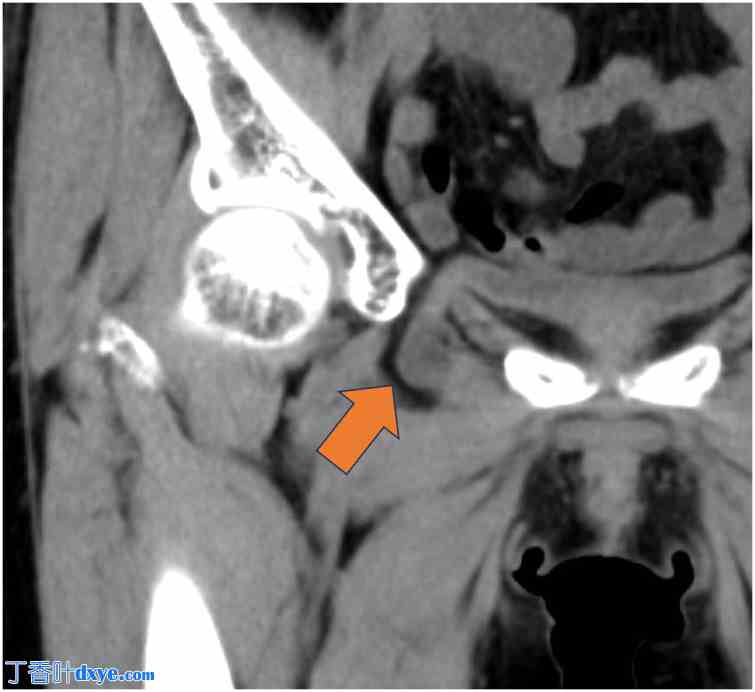

一名74岁女性被诊断为闭孔膀胱疝,并转诊至我科行手术治疗。该患者最初因便血入院,被诊断为缺血性结肠炎。诊断时进行的CT检查意外发现小肠闭孔疝(图1)。次日复查CT显示膀胱经闭孔疝出(图2)。因此,她随后被转诊至院进行进一步评估和治疗。她的缺血性结肠炎经保守治疗后痊愈。患者身高151.7 cm,体重45.3 kg,BMI为19.7。她没有与闭孔膀胱疝相关的症状。既往病史包括子宫肌瘤和阑尾炎,分别接受了腹腔镜下子宫肌瘤切除术和阑尾切除术。她不吸烟,偶尔饮酒。院CT检查证实膀胱经闭孔疝出,确诊为闭孔膀胱疝(图3)。在详细解释病情及相关风险后,患者同意接受手术治疗。

图1. 转诊医院的初始CT扫描。箭头:小肠经闭孔疝出。

1.jpg